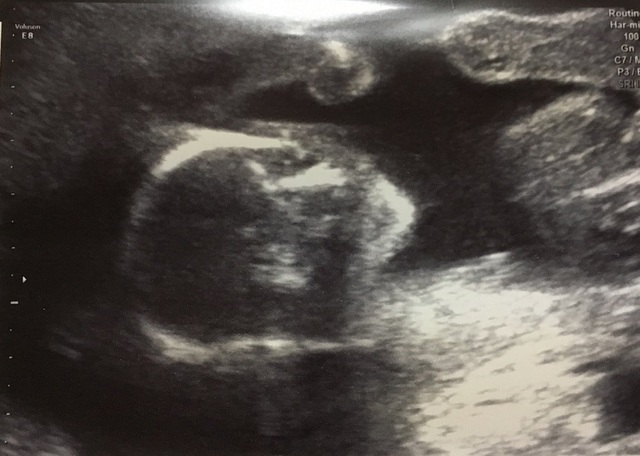

19週1日(19w1d・女の子)|shakku さん(31歳)

エコー写真撮影時のエピソード:

初めて顔が見えたエコー写真です。

お腹の中に人間がいる、妊娠してるんだなぁ(笑)と感じたエコー写真でした。

横向きで可愛いなぁと感じました。

パッと見、どうなっているかわからないので、写真に目と口、鼻を書いて母に送信しました。

母も顔が見えて嬉しそうでした。